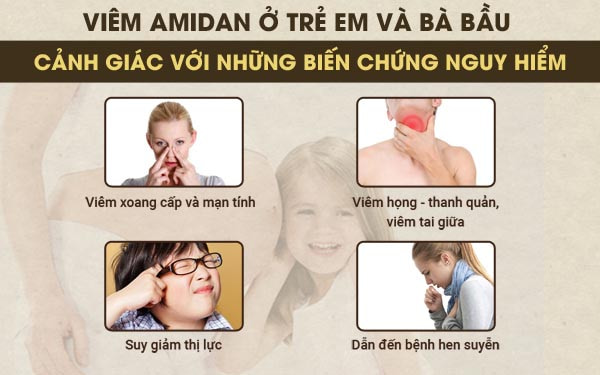

Viêm amidan dù không phải là bệnh lý nguy hiểm, nhưng nếu không có cách giải quyết kịp thời, mẹ bầu và trẻ em dễ gặp phải những tổn thương không đáng có. Nhằm hạn chế biến chứng nguy hiểm của bệnh viêm amdian, việc tìm hiểu triệu chứng, nguyên nhân và cách tiêu diệt viêm amdian cấp, mãn tính và viêm amidan có mủ từ sớm là cần thiết.